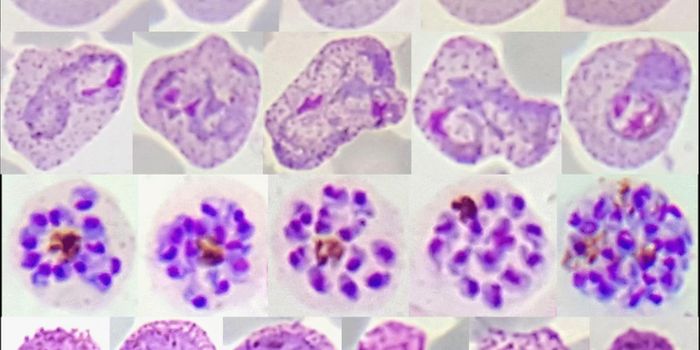

JUN 30, 2016Genetics & GenomicsIn the world of malaria infection, Plasmodium falciparum parasites will always be queen to their less lethal cousin, Pla ...